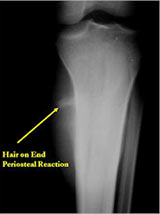

Plain X-Rays:

- Diaphyseal lesion on external surface of bone; medullary canal uninvolved

- Radiolucent mass extending into surrounding soft tissues

- Saucerized cortex with chondroblastic soft tissue mass that is usually primarily radiolucent on plain X-rays

- Periosteal reaction usually most evident feature on surface of bone (Hair on End or Sunburst appearance with spiculated pattern of calcification oriented perpendicular to the bone)

- Cortical thickening at margins of erosion (40%)

- Rarely may have Codman’s triangle

- Spiculated or sunburst periosteal reaction (due to periosteal elevation)

- Partial matrix mineralization may be seen consistent with

- chondroblastic nature

- Rare intramedullary invasion